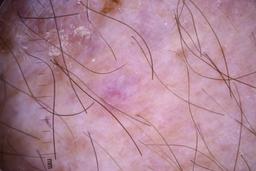

- Name: Challenge 2020: Training

- Number of images: 33,126

- Number of specified lesions: 32,701

- Number of specified patients: 2,056